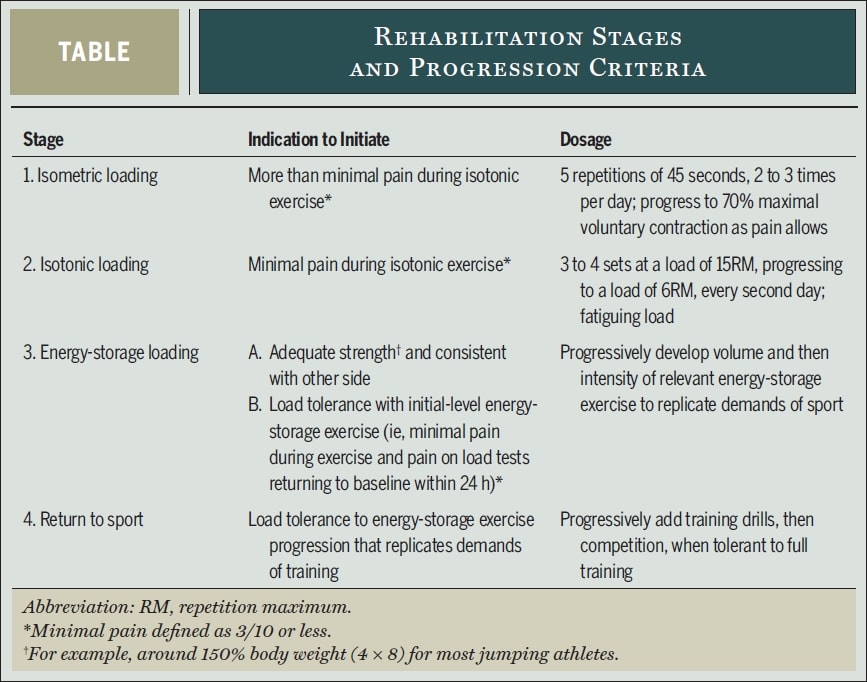

Wie könnte also ein solches schweres, langsames Widerstandsprogramm aussehen? Die Tendinopathie-Spitzenforscher Peter Malliaras, Jill Cook, Craig Purdam und Ebonie Rio schlagen in ihrem Artikel aus 2015 das folgende evidenzbasierte 4-stufige Rehabilitationsprotokoll vor:

In erster Linie sollte eine Belastungsmodifikation von hochbelastenden Energiespeicheraktivitäten, die die Schmerzen verschlimmern, vorgenommen werden. Bei Athleten, die sich mitten in der Saison befinden, sollten Umfang und Häufigkeit dieser Aktivitäten in Absprache mit dem Athleten und dem Trainer reduziert werden. Gewisse Schmerzen während und nach den Übungen wurden als akzeptabel angesehen, aber die Symptome sollten sich innerhalb von 24 Stunden nach den Übungen gelegt haben. In ihrer Arbeit verwendete Malliaras eine Wiederholung der einbeinigen Kniebeuge bis zu einer Kniebeugung von 90 Grad oder dem maximal zulässigen Winkel als Schmerz-Provokationstest, um die Belastungstoleranz auf täglicher Basis zu bestimmen. Wenn der Schmerzwert beim Belastungstest innerhalb von 24 Stunden nach der Aktivität oder Rehabilitationsmaßnahme auf den Ausgangswert zurückgegangen ist, wurde die Belastung toleriert. Wenn der Schmerz schlimmer wird, ist die Belastungsgrenze überschritten.

Schauen wir uns die einzelnen Rehabilitationsphasen genauer an:

Stufe 1 - Schmerzlinderung: Isometrische Belastung

- 5 Wiederholungen von 45 Sekunden isometrischer Quadrizepsübungen im mittleren Bereich (30-60° Kniebeugung) mit einem Bein bei 70% des MVIC 2-3x/Tag.

- Die Widerstandsfähigkeit sollte so schnell wie möglich erhöht werden.

- Spanische Hocke

- Behebung anderer Kraftdefizite entlang der kinetischen Kette

Stufe 2 - Wiederherstellung der Muskelmasse und -kraft und Einleitung der Sehnenanpassung: Isotonische Belastung

- Wenn die Quads isotonisch belastet werden können, ohne dass der Schmerz über NRS 3/10 hinausgeht, kann diese Phase eingeleitet werden.

- Schwere, langsame Widerstandsübungen zwischen 10° und 60° Kniebeugung zu Beginn und in Richtung und über 90° Beugung hinaus, wenn der Schmerz es zulässt. Dazu gehören Beinpressen, Kniebeugen, Hack-Squats, Split-Squats und sitzende Kniestrecker. Zunächst beidbeinig, dann einbeinig, sobald der Schmerz es zulässt. Kongsgaard et al. führten jeden zweiten Tag 3 bis 4 Sätze mit einem Widerstand von 15RM aus und steigerten sich bis zu 6RM. Setzen Sie die Übungen der Stufe 1 an den Tagen fort, die zwischen den schweren, langsamen Widerstandsübungen liegen.

Stufe 3 - Energiespeicherndes Laden: Erhöhung der Lasttoleranz und Verbesserung der Leistung

- Wenn eine gute Kraft erreicht ist und der Sportler eine einbeinige Belastung mit etwa 150 % des Körpergewichts toleriert (z. B. 4 Sätze mit 8 Wiederholungen einer einbeinigen Presse), kann diese Phase eingeleitet werden, wenn innerhalb von 24 Stunden nach dem Training keine Schmerzen über NRS 3/10 hinaus auftreten.

- Die Einleitung kann eine beidseitige Beinpresse mit dem 3-fachen des Körpergewichts sein (oder dem 1,5-fachen im Falle eines einzelnen Beins), da dies eine Patellakraft ausübt, die den Kräften entspricht, die bei der Landung aus einem vertikalen Sprung auftreten.

- Sprungfolgen mit Stopplandungen, Springen und Landen, Beschleunigen und Abbremsen, Schneiden und Richtungswechsel

- Das Volumen (die Anzahl der Sprünge, Kontakte) wurde vor der Intensität (Höhe, Geschwindigkeit) gesteigert.

- Führen Sie die Übungen jeden dritten Tag durch und setzen Sie die isometrische Belastung und die isotonische Belastung jeden zweiten und dritten Tag fort.

Stufe 4 - Rückkehr zum Sport

- Stufenweiser Wiedereinstieg in das Training und den Wettkampf, wobei das Training zunächst dem Umfang und der Intensität der Übungen der Stufe 3 entspricht und dann auf einen Umfang und eine Intensität gesteigert wird, die der sportartspezifischen Situation entsprechen.

- Beibehaltung der Übungen der Stufe 2 mindestens zweimal pro Woche und eventuell der Übungen der Stufe 1 vor oder nach dem Training.

Seien Sie sich bewusst, dass der gesamte Rehabilitationsprozess langwierig sein kann und manchmal mehr als 6 Monate dauert. Eine Studie von Bahr et al. (2014 ) fanden heraus, dass nur 46 % der Athleten mit Patellaspitzentendinopathie nach einem exzentrischen Trainingsprogramm über 12 Monate wieder voll trainieren konnten und schmerzfrei waren.